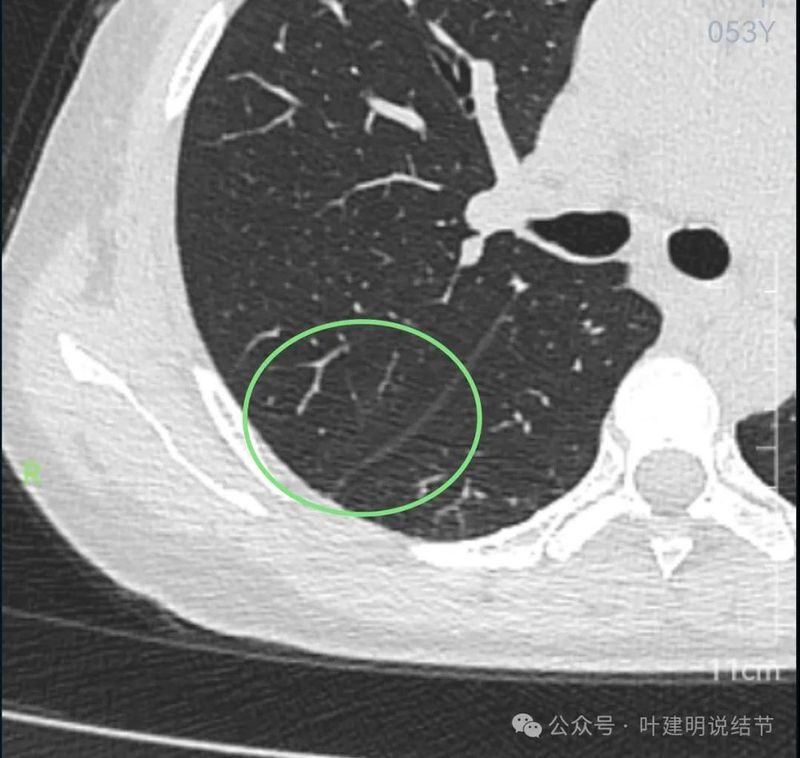

两下肺实性结节,边缘平直,右侧的以宽的基底与胸膜侧接触,两侧均无收缩力,也无膨胀感。考虑良性结节(与之前对比也无进展)。

右下很淡的微小磨玻璃结节,轮廓较清。

左下很淡也不太确切的磨玻璃影,轮廓与边界欠清。

红色的实性结节缺乏膨胀性,位于胸膜下,两侧多发,考虑良性的;黄色的密度过淡,也不是典型结节状,大概少许纤维增生或肺泡上皮增生可能性大,目前风险小;粉色的磨玻璃密度,轮廓与边界清楚,考虑肺泡上皮增生或不典型增生可能性大。总体可年度复查随访。意见供参考!